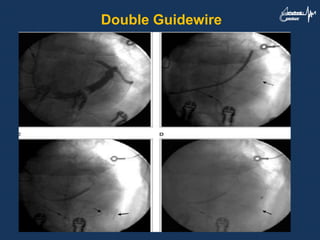

Double Guidewire

Sharply Angulated orTortuous Target Vein 1. Use an appropriately shaped inner sheath that can selectively hook the target vein 2. Other techniques include pushing the wire as much inside the vein as possible to gain extra support, or to pull the wire while advancing the lead 3. Using second stiffer wire to reduce the tortuosity and provide extra support